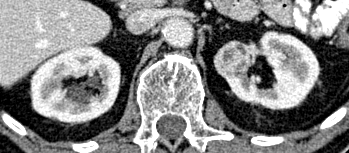

Case 00082: Early-stage benign tumor with 3D volume visualization (top) and optimal 2D slice selection (bottom)

Additional Case Study: Benign Tumor

The diagram to the right illustrates how our approach extracts the most relevant 2D slices from a 3D volume, optimizing both the quantity and quality of training data.

Diagram showing how 3D volumetric data is transformed into multiple 2D slices along different planes for optimal model training

These side-by-side comparisons show the relationship between 3D tumor volumes (top row) and their corresponding 2D slices (bottom row) for both malignant and benign cases. Our algorithm intelligently selects the most informative 2D slices from each 3D volume, capturing the key diagnostic features while generating multiple training examples from a single case.

Key insight: By converting each 3D case into multiple 2D slices, we effectively increased our training data by a factor of 8-10, with each slice carrying distinct morphological information about the tumor.